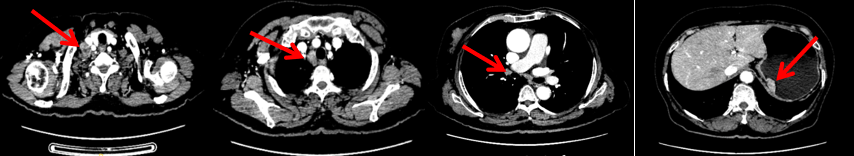

颈胸腹盆腔CT

右乳外上象限占位,考虑乳腺癌;右侧锁骨上、上纵隔及右肺门多发淋巴结转移(较大者24*15mm)。胃贲门处小弯侧胃壁明显增厚(26*12mm),考虑胃癌可能,周围脂肪间隙清;颈部未见明确异常。头颅MR未见脑转移。

1.右乳外上象限乳腺癌病灶(22*16mm),对比2023-04-14 CT(26*24mm)较前缩小,FDG代谢活跃。右侧腋窝小淋巴结(5mm),较前稍缩小,代谢不活跃。右侧锁骨上区、上纵隔淋巴结转移瘤(24*18mm),现大小同前相仿,代谢活跃(SUV:6.7)。

2024-11-5复查CT:右乳外上象限占位(11mm×9mm),较前明显缩小;上纵隔及右肺门多发淋巴结转移缩小;右锁骨上区淋巴结较前增大。余部位未见肿瘤转移及复发征象。